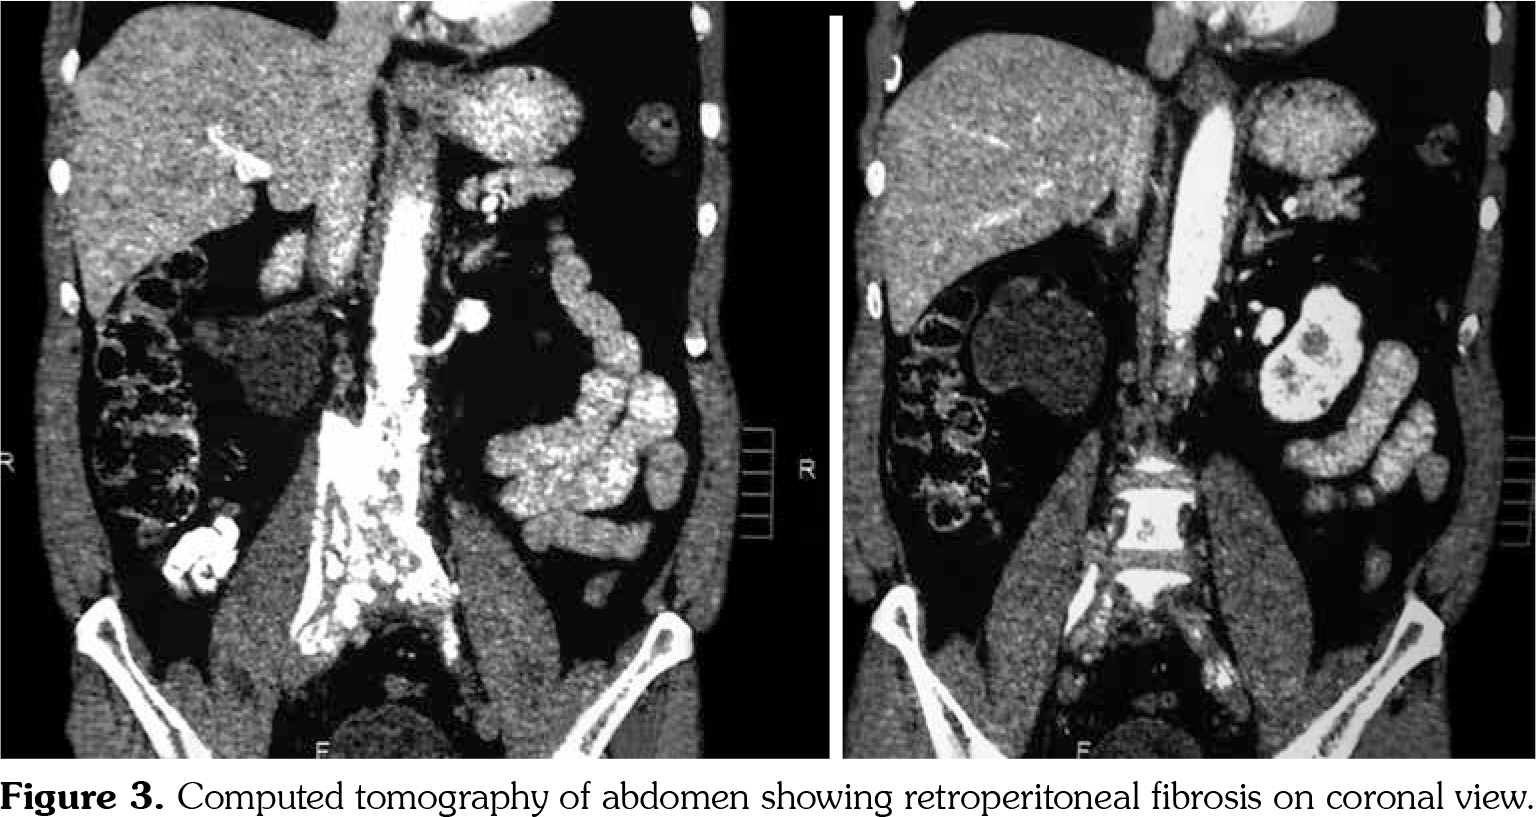

On investigations, his complete blood count was normal. Erythrocyte sedimentation rate was 88 mm in first hour. Random blood sugar was 93 mg/dL. His serum urea was 26 mg/dL and serum creatinine was 1.1 mg/dL. Liver function tests were within normal limits. Chest X-ray revealed non-homogenous opacities in bilateral lung fields. Pulmonary function tests revealed forced expiratory volume in one second (FEV1) of 61% and forced vital capacity (FVC) of 73%. FEV1/FVC ratio was 84%. Two-dimensional echocardiography was within normal limits. Ultrasonography of the abdomen revealed small-sized right kidney (6.9x2.9 cm) with dilated pelvi-calyceal system and dilated proximal ureter. Computed tomography (CT) of the abdomen revealed medial deviation of right ureter and presence of retroperitoneal soft tissue along infra-renal aorta and peri-caval area with calcification extending up to iliac vessels suggestive of RPF (Figures 1, 2, 3, and 4). High-resolution CT of the chest confirmed presence of interstitial lung disease (ILD). ANA profile (ENA) revealed that anti-U1 snRNP was strongly positive. Rest of the autoantibodies were negative. His serum immunoglobulin G levels were within normal limits. Thus, we arrived at a diagnosis of MCTD with RPF and ILD. He was started on mycophenolate 720 mg twice daily, hydroxychloroquine 200 mg once daily and deflazacort 6 mg once daily for MCTD, pirfenidone 400 mg twice daily for ILD and tamoxifen 20 mg once daily for RPF. On follow-up at six months, he was doing physically well. His symptoms of cough were reduced and dyspnea improved from NYHA class IV to class II. Repeat pulmonary function tests revealed FEV1 of 59%, FVC of 71% and FEV1/FVC ratio of 84%. However, repeat ultrasonography of the abdomen did not reveal any significant change in pelvi- calyceal system.

In 1972, Sharp et al.,[1] recorded a group of patients who had clinical features of SLE, SSc and PM with high titers of anti-extractable nuclear antigen antibody. They published it as a new disease entity: MCTD. Since then, there has been an increasing number of classification criteria published for the diagnosis of MCTD, namely, Kasukawa et al.[3] Alarcon-Segovia and Villareal[4] and Kahn and Appelboom.[5] There has been no consensus on clinical features owing to varied manifestations and frequent overlap of symptoms with other autoimmune conditions. However, high titers of antibodies against U1 snRNP have been found in most patients.[6] Our patient had symptoms of dysphagia, epistaxis and ocular sicca coupled with high titers of anti-U1 snRNP which led us to the diagnosis of MCTD. He also had pulmonary involvement in the form of ILD. One study showed 47% of cases of MCTD to have ILD.[7] The most frequent histological picture seen is non-specific interstitial pneumonia, followed by usual interstitial pneumonia and lymphocytic interstitial pneumonia.[8] RPF was first reported by Ormond[9] in 1948. It is a rare condition characterized by inflammation and fibrosis of the retroperitoneum, around the infra-renal portion of abdominal aorta and iliac arteries and usually entraps ureters and inferior vena cava.[10] A recent study reported incidence of RPF around 1.3 per 100,000 population per year in Netherlands.[11] The mean age of presentation is around 50 years with male predominance (2:1-3:1). Abdominal CT and magnetic resonance imaging are the investigations of choice for the diagnosis of RPF and they reveal a homogenous mass near the lower abdominal aorta and iliac arteries that surround and displace the ureters medially. Medical therapies for RPF include steroids, tamoxifen, other immunosuppresives such as azathioprine, mycophenolate and anti-CD20 antibody such as rituximab. In one single-center prospective observational study of 55 patients with RPF treated with tamoxifen monotherapy for a minimum of two years, 47 (85%) patients reported substantial resolution of symptoms after a median treatment duration of three weeks. There was a mass regression in 39 (71%) patients at four months and 47 (85%) patients at eight months of follow-up, respectively. Recurrence- free survival in patients with treatment success after post-treatment follow-up of 21 months was 68%.[12] To our knowledge, there is no previously published case report on presence of RPF in a patient of MCTD. This is indeed a rare occurrence.